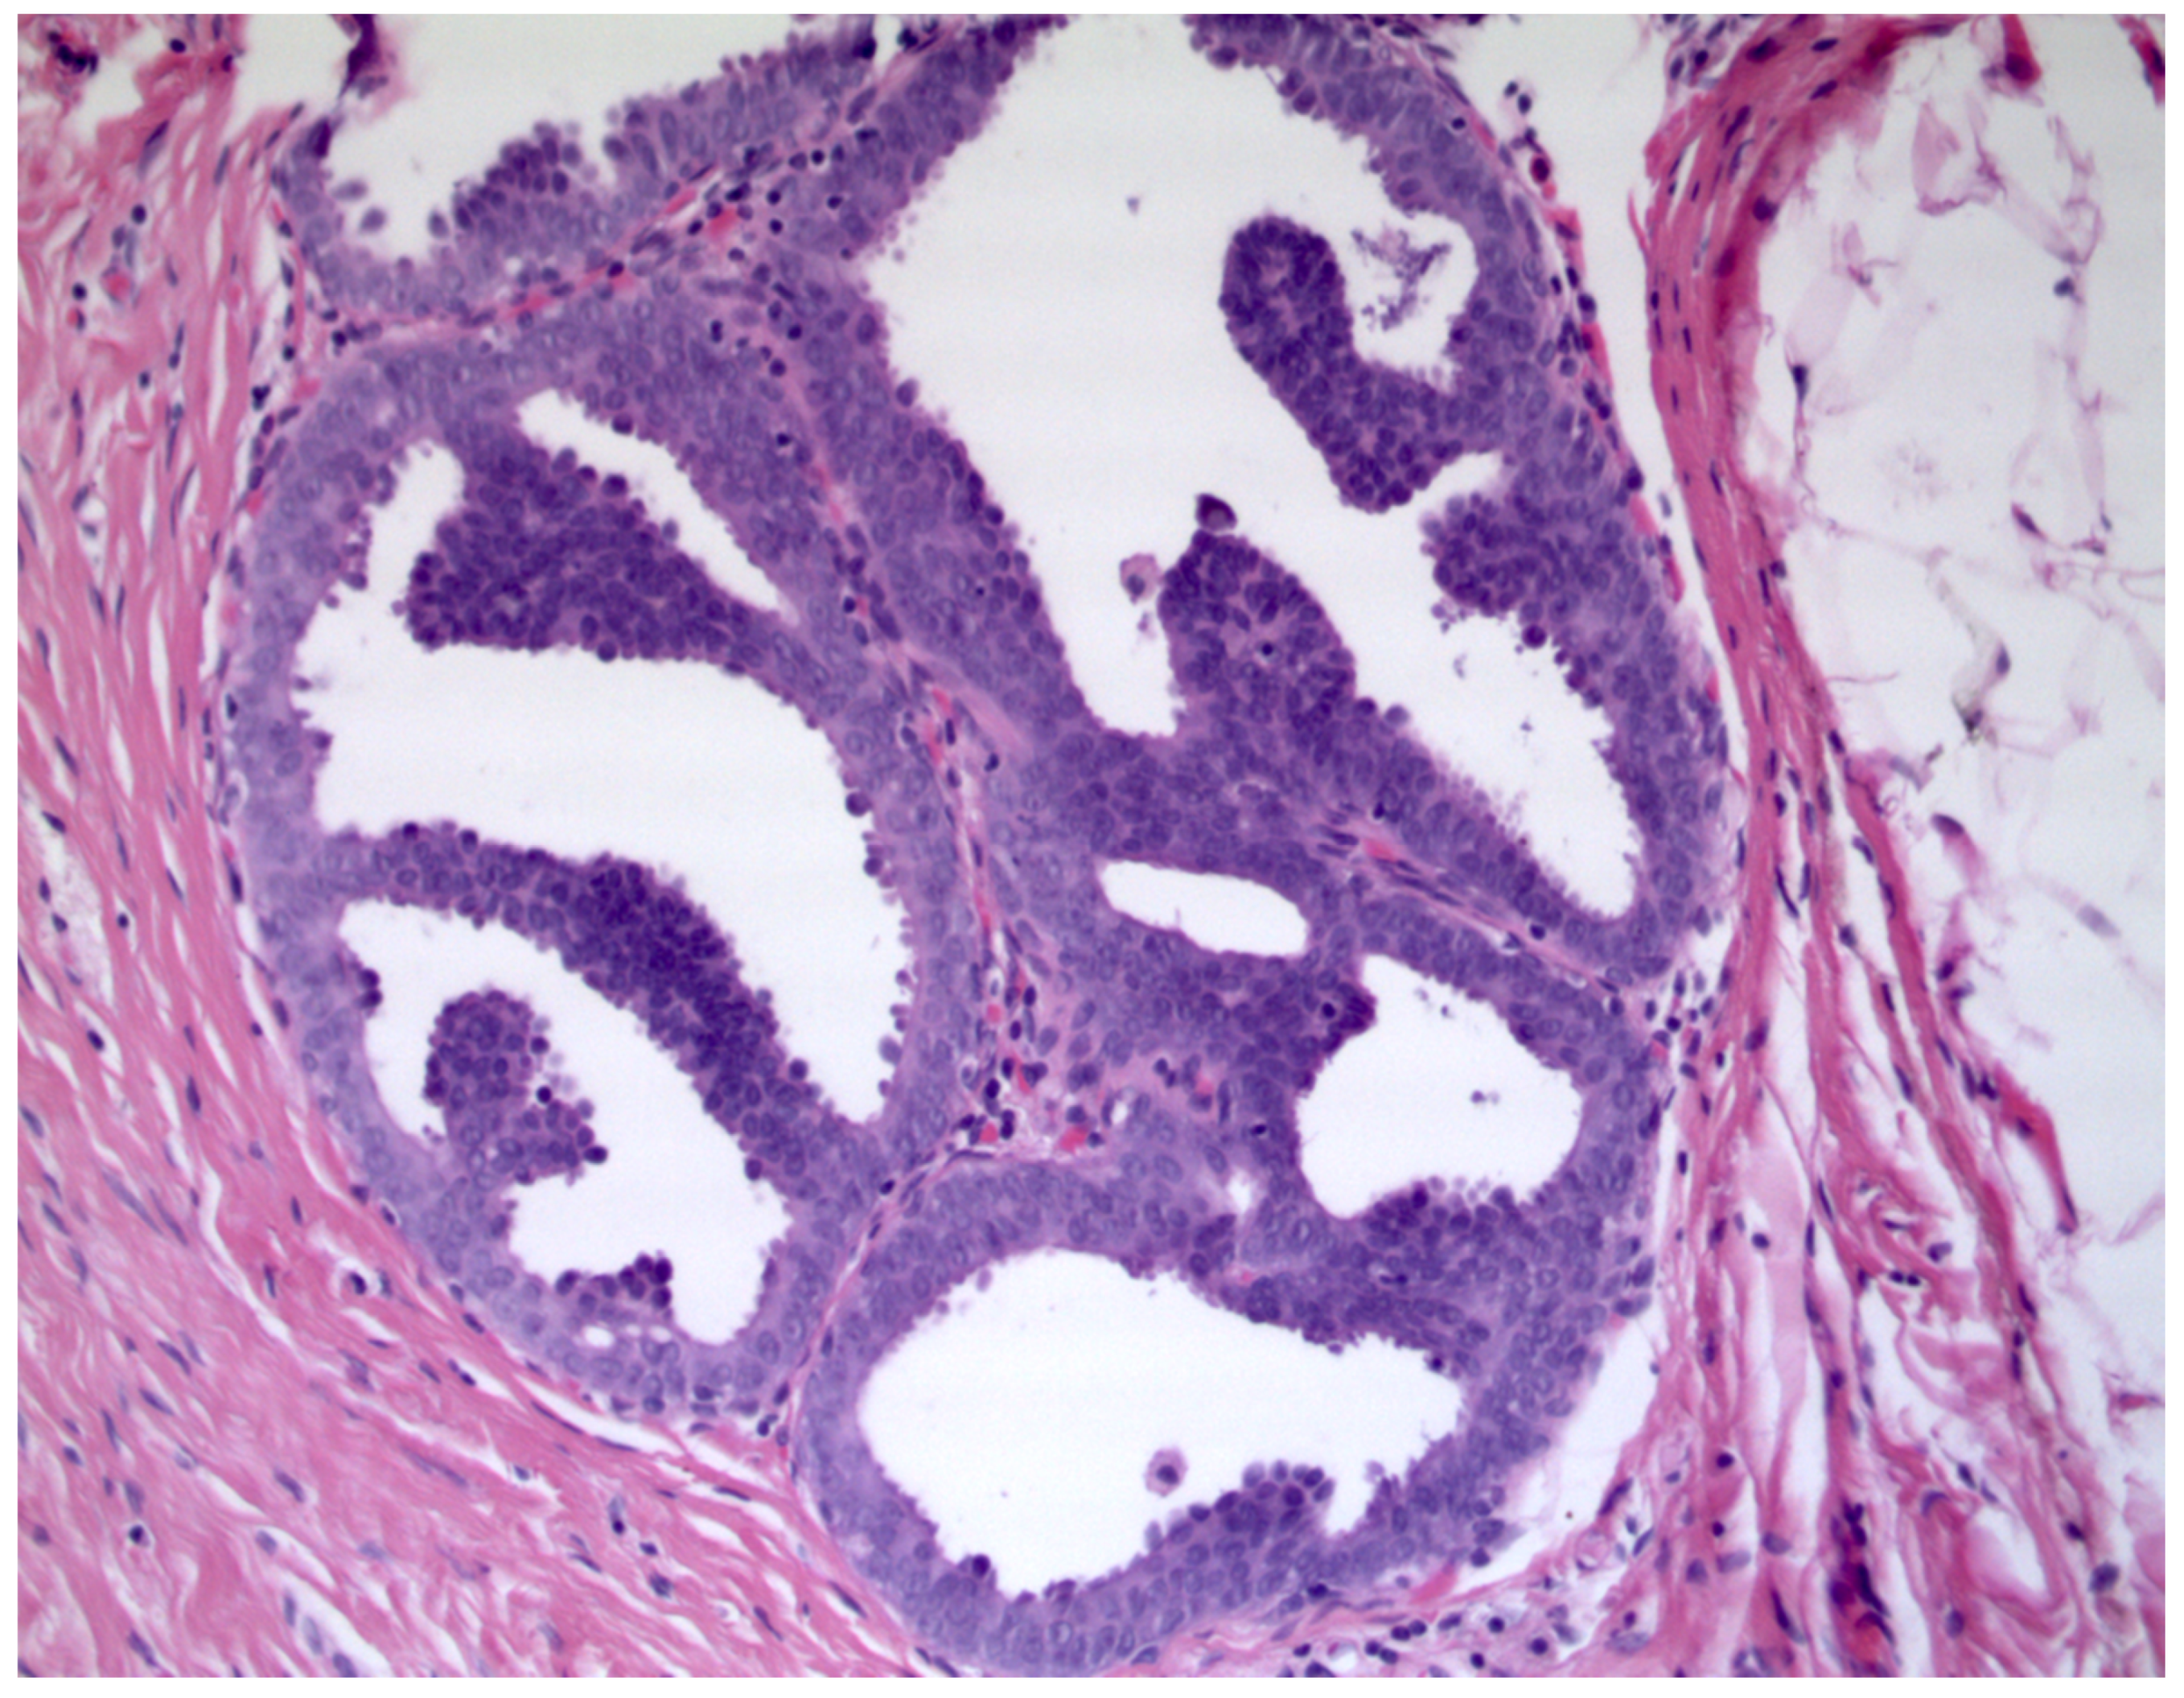

- Simpson, J.F. Update on atypical epithelial hyperplasia and ductal carcinoma in situ. Pathology 2009, 41, 36–39. [Google Scholar] [CrossRef] [PubMed]